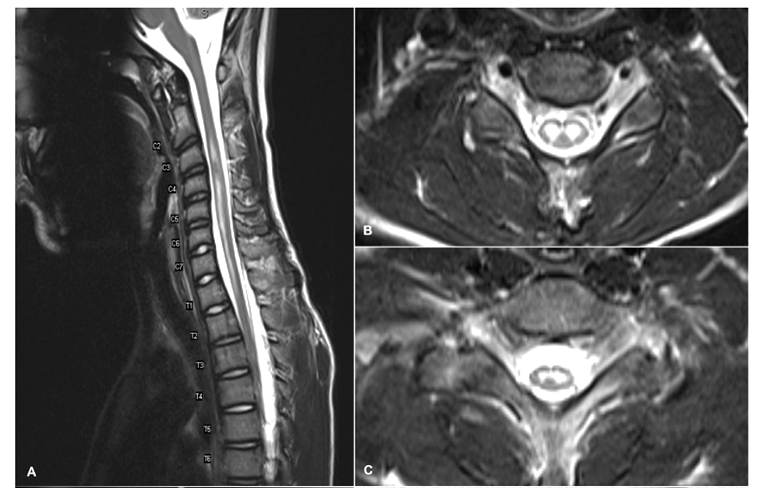

Q10: 41 year old patient presents with a rapid onset of paraplegia. He is found to be HIV positive. CSF shows elevated total protein (0,8 g/L), a mild pleocytosis (19 lymphocytes/µl), and a glucose value of 3.2. Oligoclonal bands were negative. T1 weighted s.